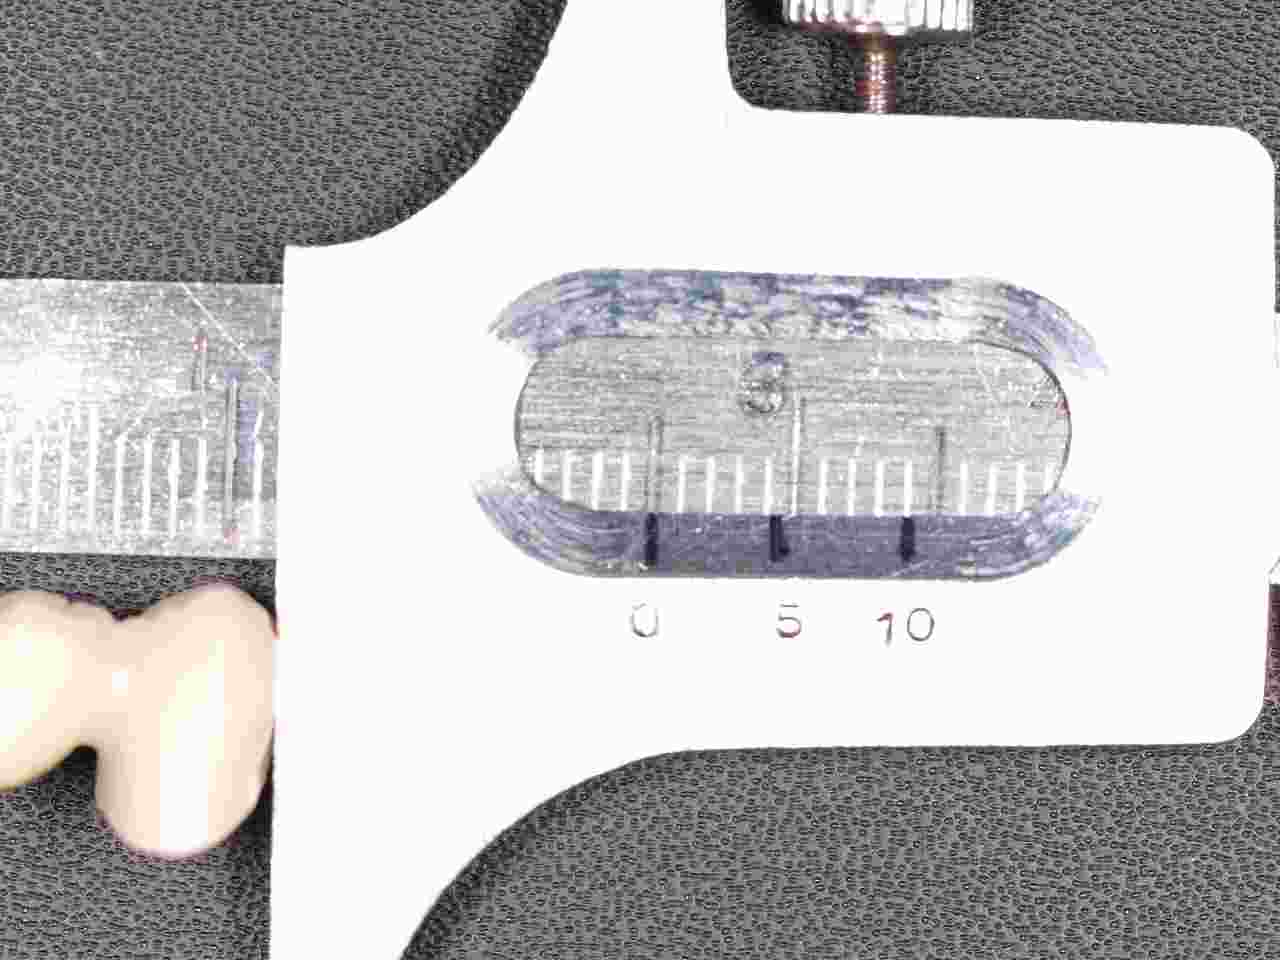

ジルコニアフレームを使用したジルコニアブリッジも6歯程度まででそれ以上になると従来通りのメタルボンドに切り替えるようにしています。 ワンピースではフレイムの適合、制度が落ちる為郎着作業が必要となりジルコニアは蝋着ができないことが理由に挙げられます。|お知らせ |広島市安佐南区の歯科医院

ジルコニアフレームを使用したジルコニアブリッジも6歯程度まででそれ以上になると従来通りのメタルボンドに切り替えるようにしています。 ワンピースではフレイムの適合、制度が落ちる為郎着作業が必要となりジルコニアは蝋着ができないことが理由に挙げられます。

ジルコニアフレームを使用したジルコニアブリッジも6歯程度まででそれ以上になると従来通りのメタルボンドに切り替えるようにしています。 ワンピースではフレイムの適合、制度が落ちる為郎着作業が必要となりジルコニアは蝋着ができないことが理由に挙げられます。